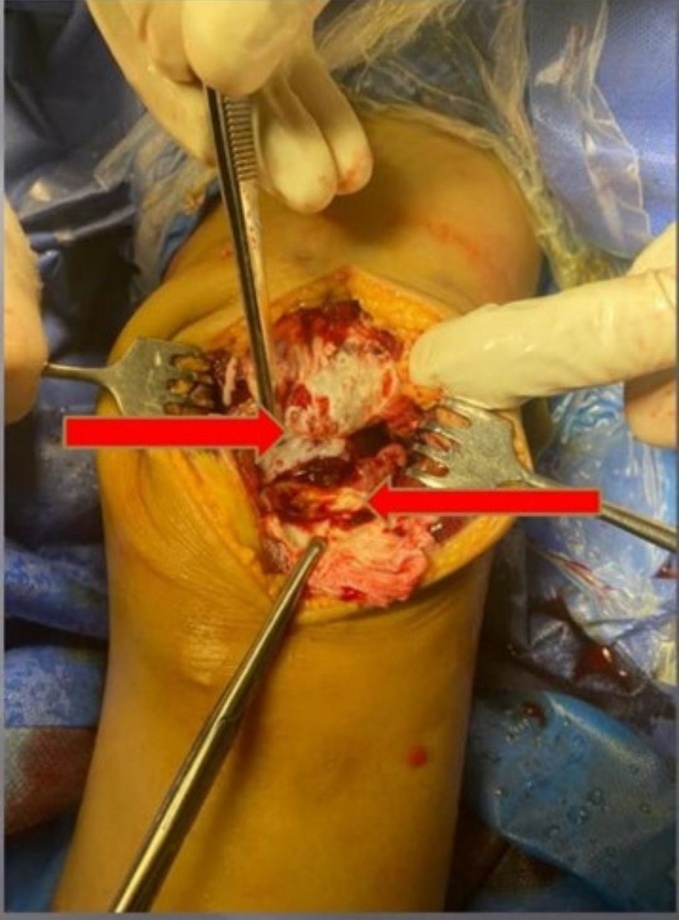

In both cases, the inferior pole of the patella demonstrated an avulsed osteochondral fragment involving approximately one-third of the articular cartilage and half of the periosteal surface. The patellar retinaculum was found to be torn and shredded, which complicated visualization, a finding commonly associated with sleeve fractures. Reduction was achieved under direct vision using reduction clamps to restore the patellar tendon–bone continuity and anatomical alignment of the osteochondral fragment.

Two parallel transosseous tunnels were created from the inferior to the superior patellar cortex using a 2.0-mm drill bit. Suture passage was facilitated with ACL wire passers to minimize fraying. Two No. 5 non-absorbable polyester sutures (Ethibond Excel®, Ethicon, USA) were woven in a Krackow fashion through the patellar tendon and osteochondral fragment. The four free suture limbs were shuttled proximally through the transosseous tunnels and tied securely over the superior pole of the patella, achieving stable fixation. The torn medial and lateral retinacula were repaired with absorbable sutures. Anatomical reduction and patellar height were confirmed both visually and fluoroscopically, using the contralateral knee as a reference. The wounds were closed in layers, and a long leg cylinder cast made of fiberglass was applied in full extension to protect the repair. (Figure 4-6)

In these two cases, the inferior pole of the patella was not large enough to be securely fixed with screws (tiny size not more than 1*1 cm2). Transosseous tunnel sutures were utilized to fix the inferior pole to the main proximal fragment.